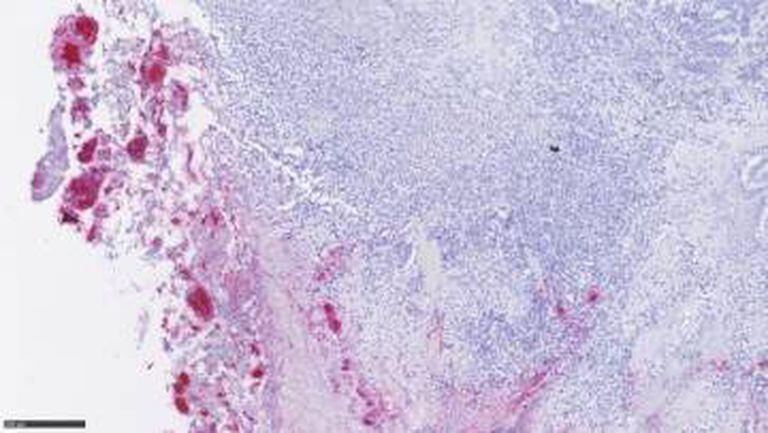

A equipe de Nuciforo detectou a Fusobacterium em 70% de uma amostra de 200 tumores colorretais humanos. Nas metástases hepáticas desses tumores primários também aparecem as mesmas cepas da bactéria, dentro das próprias células tumorais.

“Se não existisse uma relação, seria quase impossível que a flora microbiana de um tumor no cólon fosse igual à de um tumor no fígado. São órgãos totalmente diferentes”, diz o pesquisador. O trabalho, publicado na sexta-feira na revista Science, é comandado por cientistas do Instituto do Câncer Dana-Farber, em Boston (EUA).